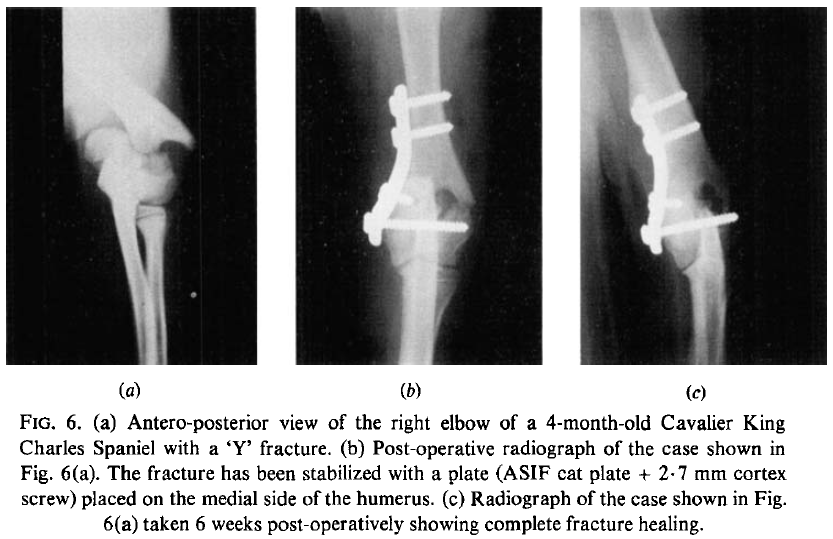

Condylar fractures of the humerus in the dog; a review of 133 cases. H. R. Denny. J. Small Anim. Pract. 1983;24:185-197. Quote: Case histories have been reviewed of 133 dogs with condylar fractures of the humerus. The fractures were divided into three types: lateral condylar, medial condylar and intercondylar. For each type the breed and age prevalence, the cause of fracture, the method of fixation and the results of treatment have been recorded. ... Seventy-four dogs had fractures of the lateral condyle. The injury was seen in 20 breeds and Spaniels (38 per cent) were most frequently affected [including 5 Cavalier King Charles Spaniels]. The sex ratio was equal. Sixty-seven per cent of cases were under a year of age and the peak age prevalence was 4 months (Table 2). The commonest cause of fracture was a fall; other causes are listed in Table 3. In 65 dogs the fracture was stabilized with a single lag screw driven through the lateral condyle into the medial condyle." See Figure 6 (below) of the right elbow of a 4-month-old cavalier.